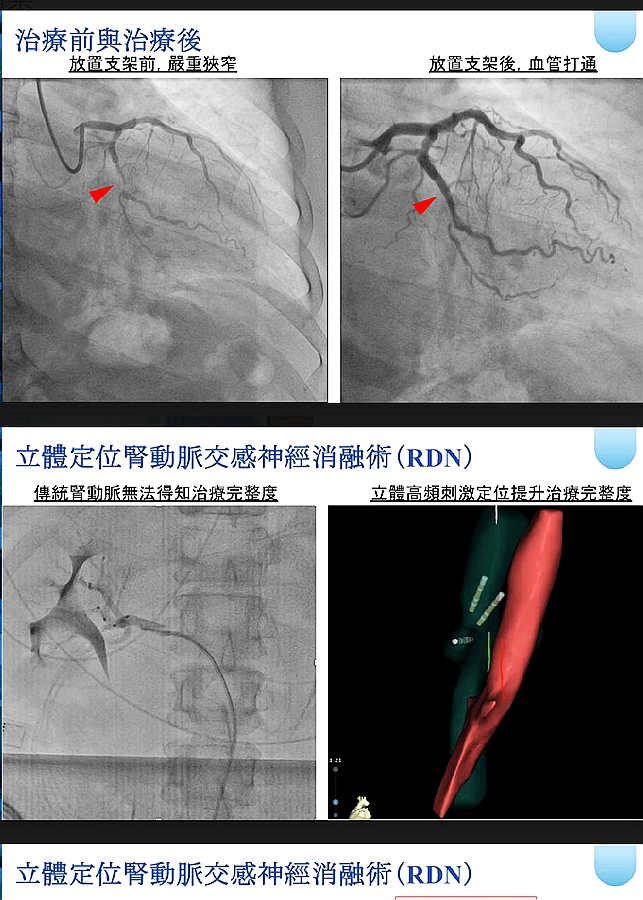

患者體態良好但血壓長期飆破180 mmHg,伴隨劇烈頭痛與失眠。心臟內科暨導管室主任鍾偉信醫師檢查後發現,他除了血壓失控,低密度膽固醇(LDL)異常偏高、冠狀動脈亦有明顯狹窄。為避免血管進一步受損,團隊建議施行立體定位腎動脈交感神經消融術(RDN),並同步植入第三代鎂合金可吸收支架。

治療後患者血壓即降,狹窄血管成功撐開,且未來支架吸收後,血管可恢復自然彈性。 【解決高血壓源頭、修復狹窄血管】 該患者雖規律服藥與追蹤,但多年來始終無法有效控制血壓,因此輾轉來到市立醫院尋求治療。經心血管中心安排精密檢查後,由鍾偉信、簡思齊、陳琦棟醫師施以立體定位腎動脈交感神經消融術改善頑固型高血壓,同時針對冠狀動脈病灶植入鎂合金可吸收支架。

【年輕患者首選:可吸收支架保留血管彈性】 年輕患者若以傳統金屬支架治療,血管會因永久性金屬結構而失去自然舒縮能力。第三代鎂合金可吸收支架初期能穩定撐開血管,一年內約99%會被身體吸收,不會殘留異物或造成長期發炎,對保留未來血管健康十分有利。但前提須血管無嚴重鈣化、長度短、無大分支之情形,才能評估使用。